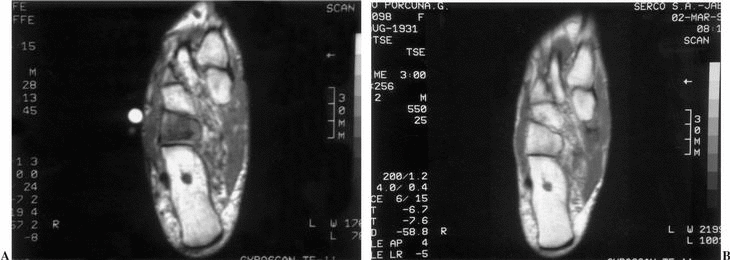

Mujer de 66 años de edad que acude a consulta presentando dolor en el pie derecho de varios meses de evolución. No refería antecedente traumático ni médico de interés. A la exploración física presentaba una tumoración en el borde externo del pie. El estudio de laboratorio mostraba únicamente discreto incremento de la velocidad de sedimentación globular (VSG) (19 mm/h). La radiografía del pie fue normal (fig. 1). En la gammagrafía ósea se apreció incremento de la captación del trazador en el cuboides (fig.2). En la RM había disminución de la intensidad de la señal en T1 e incremento en T2 a nivel de la esponjosa del cuboides acompañado de pequeño edema de partes blandas periféricas (fig. 3).

Figura 3. Imágenes de resonancia magnética (RM) del caso que se describe: (A) RM del pie derecho en T1 que muestra disminución de la señal (hueso negro) al inicio del proceso en cuboides. Se llegó al diagnóstico de osteoporosis transitoria. (B) Misma proyección en T1 al año de evolución. Se observa la normalización de la señal.

Se realizó diagnóstico diferencial con fractura de estrés, metástasis, osteomielitis y necrosis avascular, siendo descartados tras la realización de los estudios con gammagrafía ósea (tecnecio-99 metaestable y galia-67) y RM y analítica. La paciente fue tratada sintomáticamente con antiinflamatorios no esteroideos (AINE) y reposo relativo. Los síntomas cedieron gradualmente en unos 7 meses, con RM normalizada al año del inicio del proceso (fig. 3).